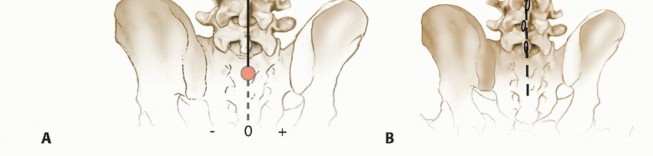

Coronal balance: the relationship between the C7 plumb line and center of S1 on PA views (FIG 4)

Sagittal balance: the relationship between the C7 plumb line and center of S1 on lateral views (FIG 7)

* **FIG 7 • Sagittal balance is evaluated on the standing lateral radiograph. It is measured as the anterior (positive) or posterior (negative) distance between the C7 plumb line and the center of the L5-S1 disc space.**